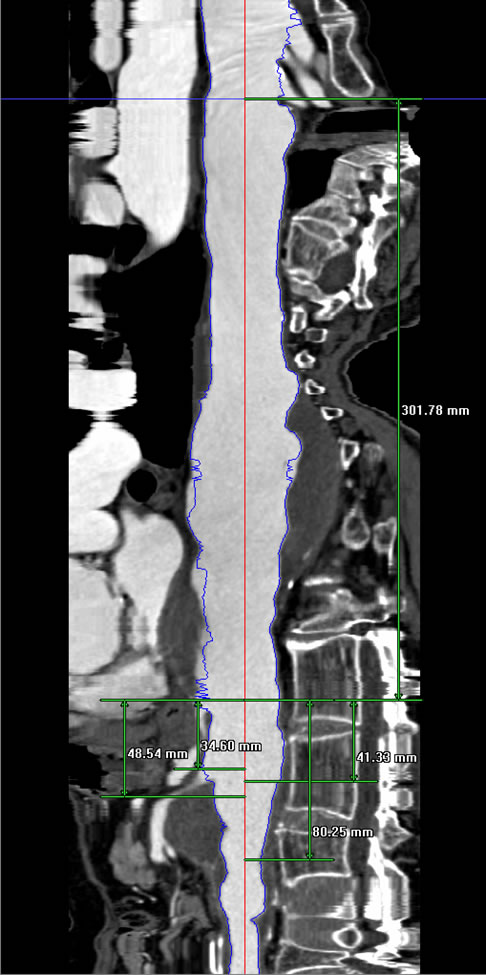

The perioperative complications of TAAA repair have not been eliminated but their incidence is reduced and include renal dysfunction, respiratory failure, stroke, MI, and spinal cord injury [2]. Other late complications include endoleaks and therefore all patients need regularly scheduled follow-up CT imaging at months 1, 6, 12 and annually (Figure 5).